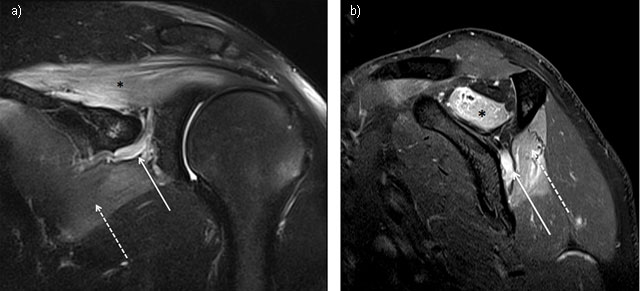

Figure 1

Suprascapular neuropathy at the scapular notch in a young judoka athlete showing typical edema denervation pattern of acute neuropathy on MRI. High signal intensity fluid is observed in fluid-sensitive sequences of both supraspinatus (star) and infraspinatus (dashed arrow). Notice the dilatation of suprascapular veins satellite (arrow). (1a = FIGURE 1 uploaded online manuscript) – Coronal (1b = FIGURE 2 uploaded online manuscript) – sagittal Short Tau Inversion recovery MRI (STIR) images.